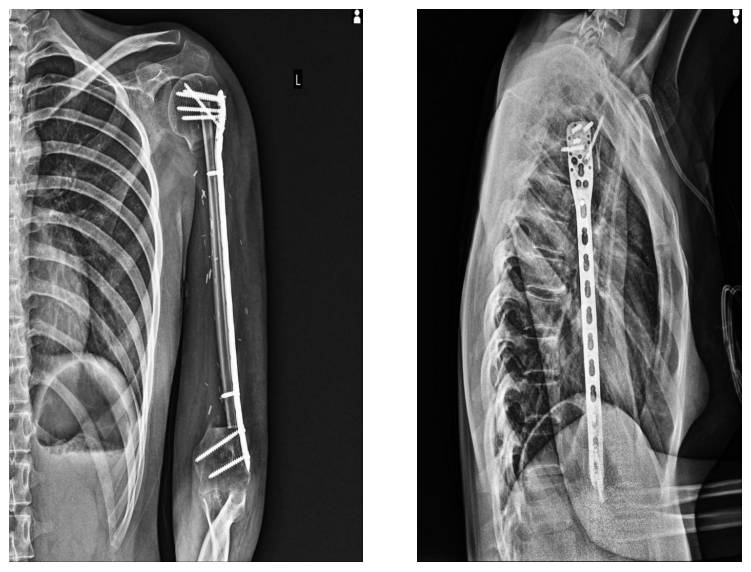

Ameliyat Sonrası: Röntgende rezeksiyon sonrası uygulanan vaskülerize fibula ve plak fiksasyonu görülmekte